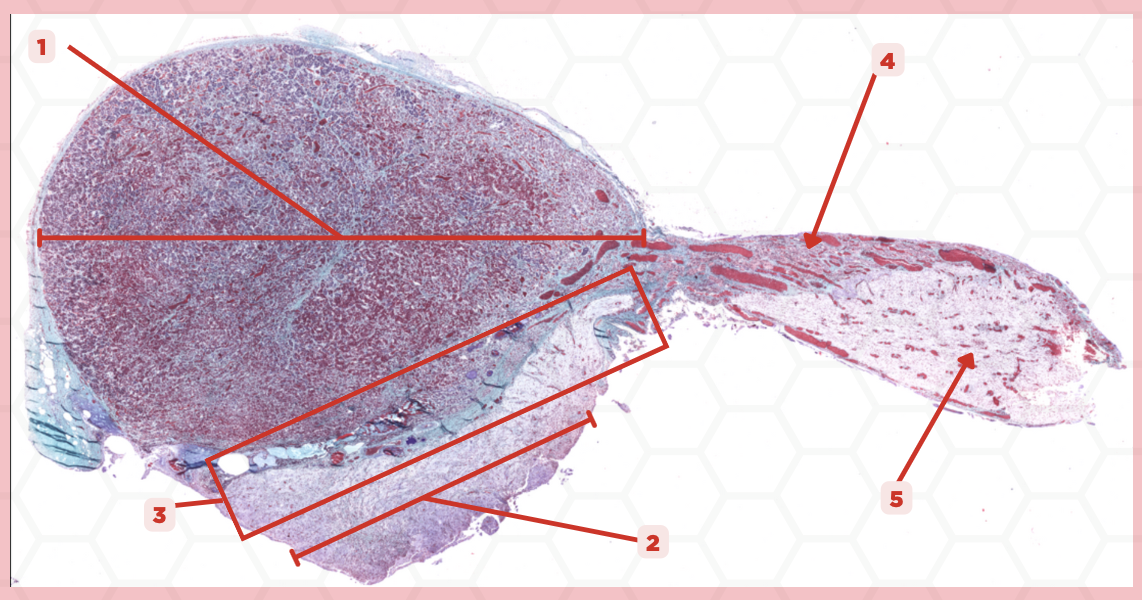

Pituitary

Identify the specimen.

Anterior Lobe

Identify the structure labeled as 1.

Posterior Lobe

Identify the structure labeled as 2.

Intermediate Lobe

Identify the structure labeled as 3.

Pars Tuberalis

Identify the structure labeled as 4.

Pituitary Stalk

Identify the structure labeled as 5.